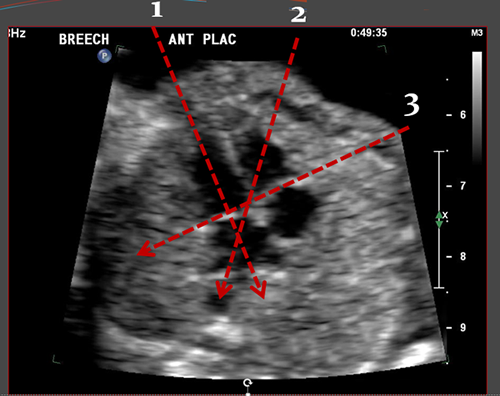

Above. 11 6/7 weeks gestation. Note the anterior placenta and the amnion chorion separation from the chorionic plate. The anechoic area represents fluid and or blood.

Above. First trimester SCH (subchorionic bleed). The relative positions of the amnion and chorion are illustrated. There is an extensive anechoic collection of fluid and blood in the subchorionic space.